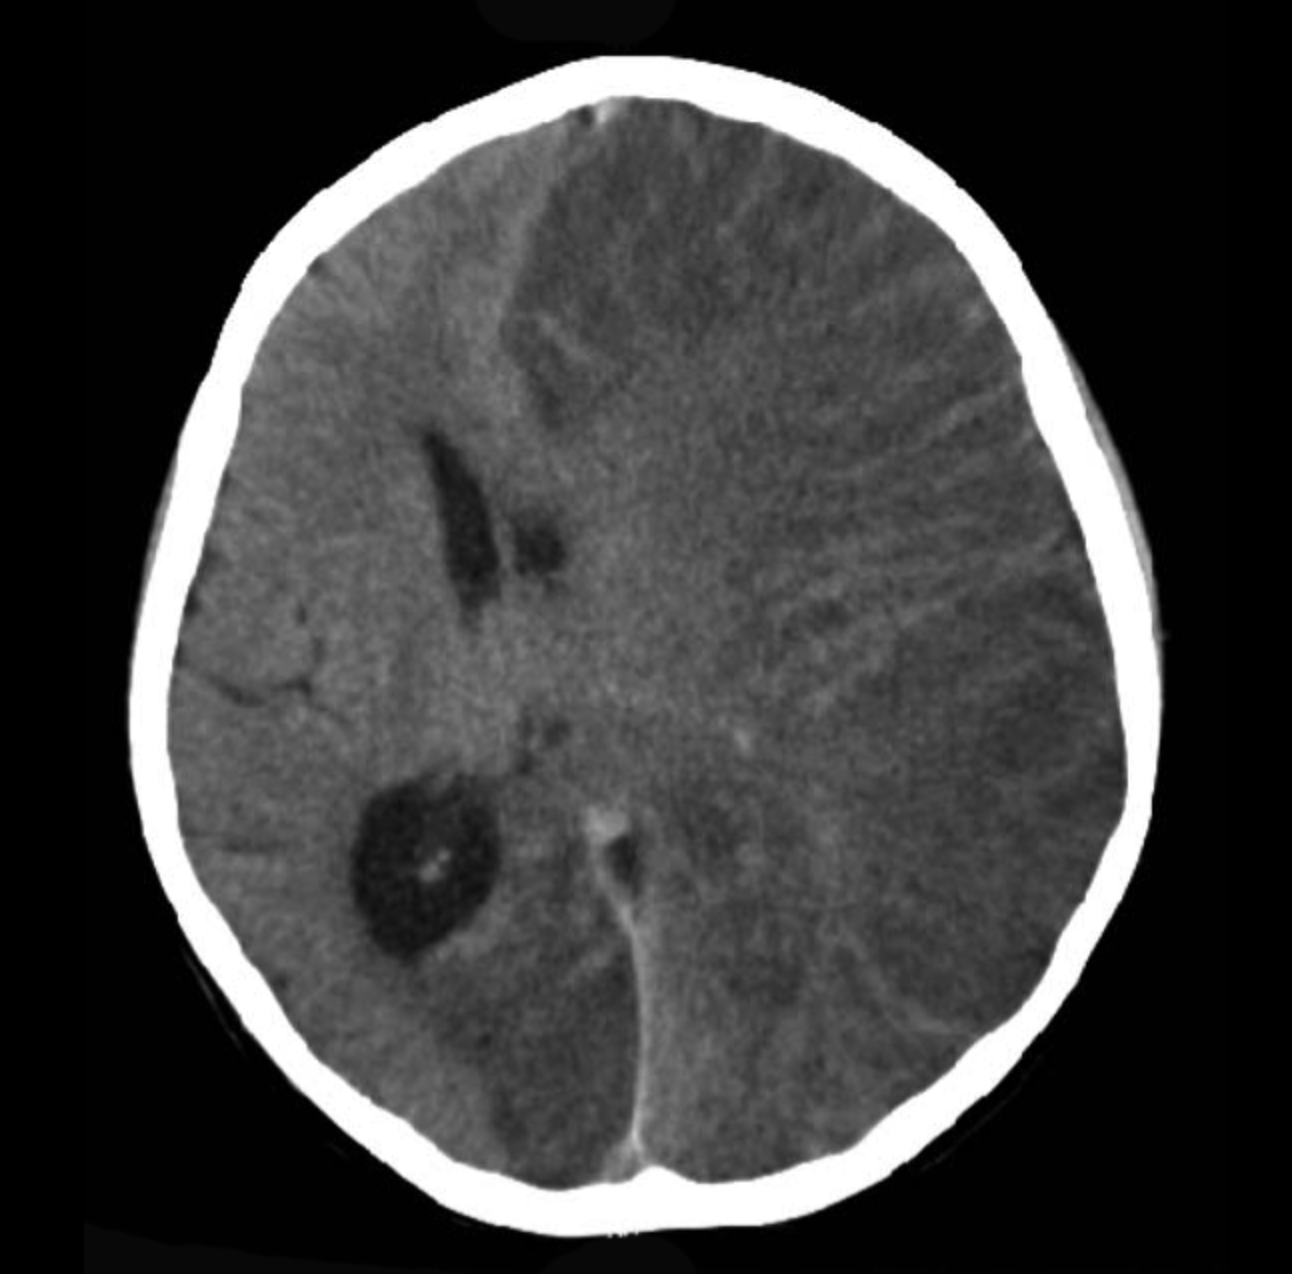

Central nervous system (CNS)- targeted inflammation characterised by increased T cell infiltration is the most consistent immunopathology associated with RE. Based on this Kebir et al., hypothesised that injecting NSG mice with peripheral blood mononuclear cells (PBMCs) from RE patients would induce RE. Indeed researchers observed that injecting mice with cells and not plasma from RE patients resulted in development of seizures in 84% of NSG mice engrafted with PBMC from RE patients. Using flow cytometry analysis of brain samples from mice, researchers demonstrated that IFN-γ, IL-17 and granzyme-B expressing CD4 T cells and HLA-DR+ lymphocytes contribute to CNS inflammation and development of seizures.